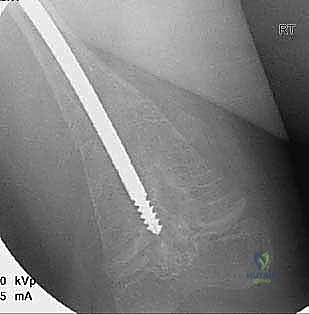

الدليل التفصيلي لخطوات العملية الجراحية: بضع العظم عبر الجلد والمسامير التلسكوبية

تُعد هذه العملية من أدق العمليات في جراحة عظام الأطفال، وتتطلب مهارة استثنائية كما هو الحال مع البروفيسور محمد هطيف. يتكون المسمار التلسكوبي (Fassier-Duval) من جزأين يتداخلان ببعضهما البعض (مثل التلسكوب). يتم تثبيت أحد الأطراف في أعلى العظم والطرف الآخر في أسفله. عندما ينمو العظم، ينزلق الجزء الداخلي من المسمار للخارج، مما يسمح للعظم بالنمو الطبيعي دون أن ينثني أو ينكسر.

الخطوة الثالثة: بضع العظم المتعدد عبر الجلد (Multiple Percutaneous Osteotomies)

بدلاً من فتح الساق بالكامل، يقوم الدكتور هطيف بعمل ثقوب صغيرة جداً (مليمترات) في الجلد. باستخدام أدوات دقيقة جداً (مثل الإزميل الدقيق أو المثقاب المتخصص)، يتم قطع العظم في أماكن التقوس من الداخل دون إتلاف الأنسجة الرخوة أو العضلات المحيطة. هذا يحافظ على التروية الدموية للعظم (Periosteum)، مما يسرع من التئام العظم بشكل مذهل.

الخطوة الرابعة: إدخال المسمار التلسكوبي

بعد تقويم العظم وجعله مستقيماً كحبات المسبحة على خيط، يتم إدخال السلك الدليلي (Guide Wire). ثم يتم إدخال الجزء الخارجي (الأنثوي) من المسمار التلسكوبي وتثبيته في الجزء العلوي من العظم (Epiphysis).

بعد ذلك، يتم إدخال الجزء الداخلي (الذكري) من المسمار عبر الجزء السفلي من العظم وتثبيته في المشاشة السفلية. هذا التصميم العبقري يضمن حماية العظم بالكامل من الداخل.